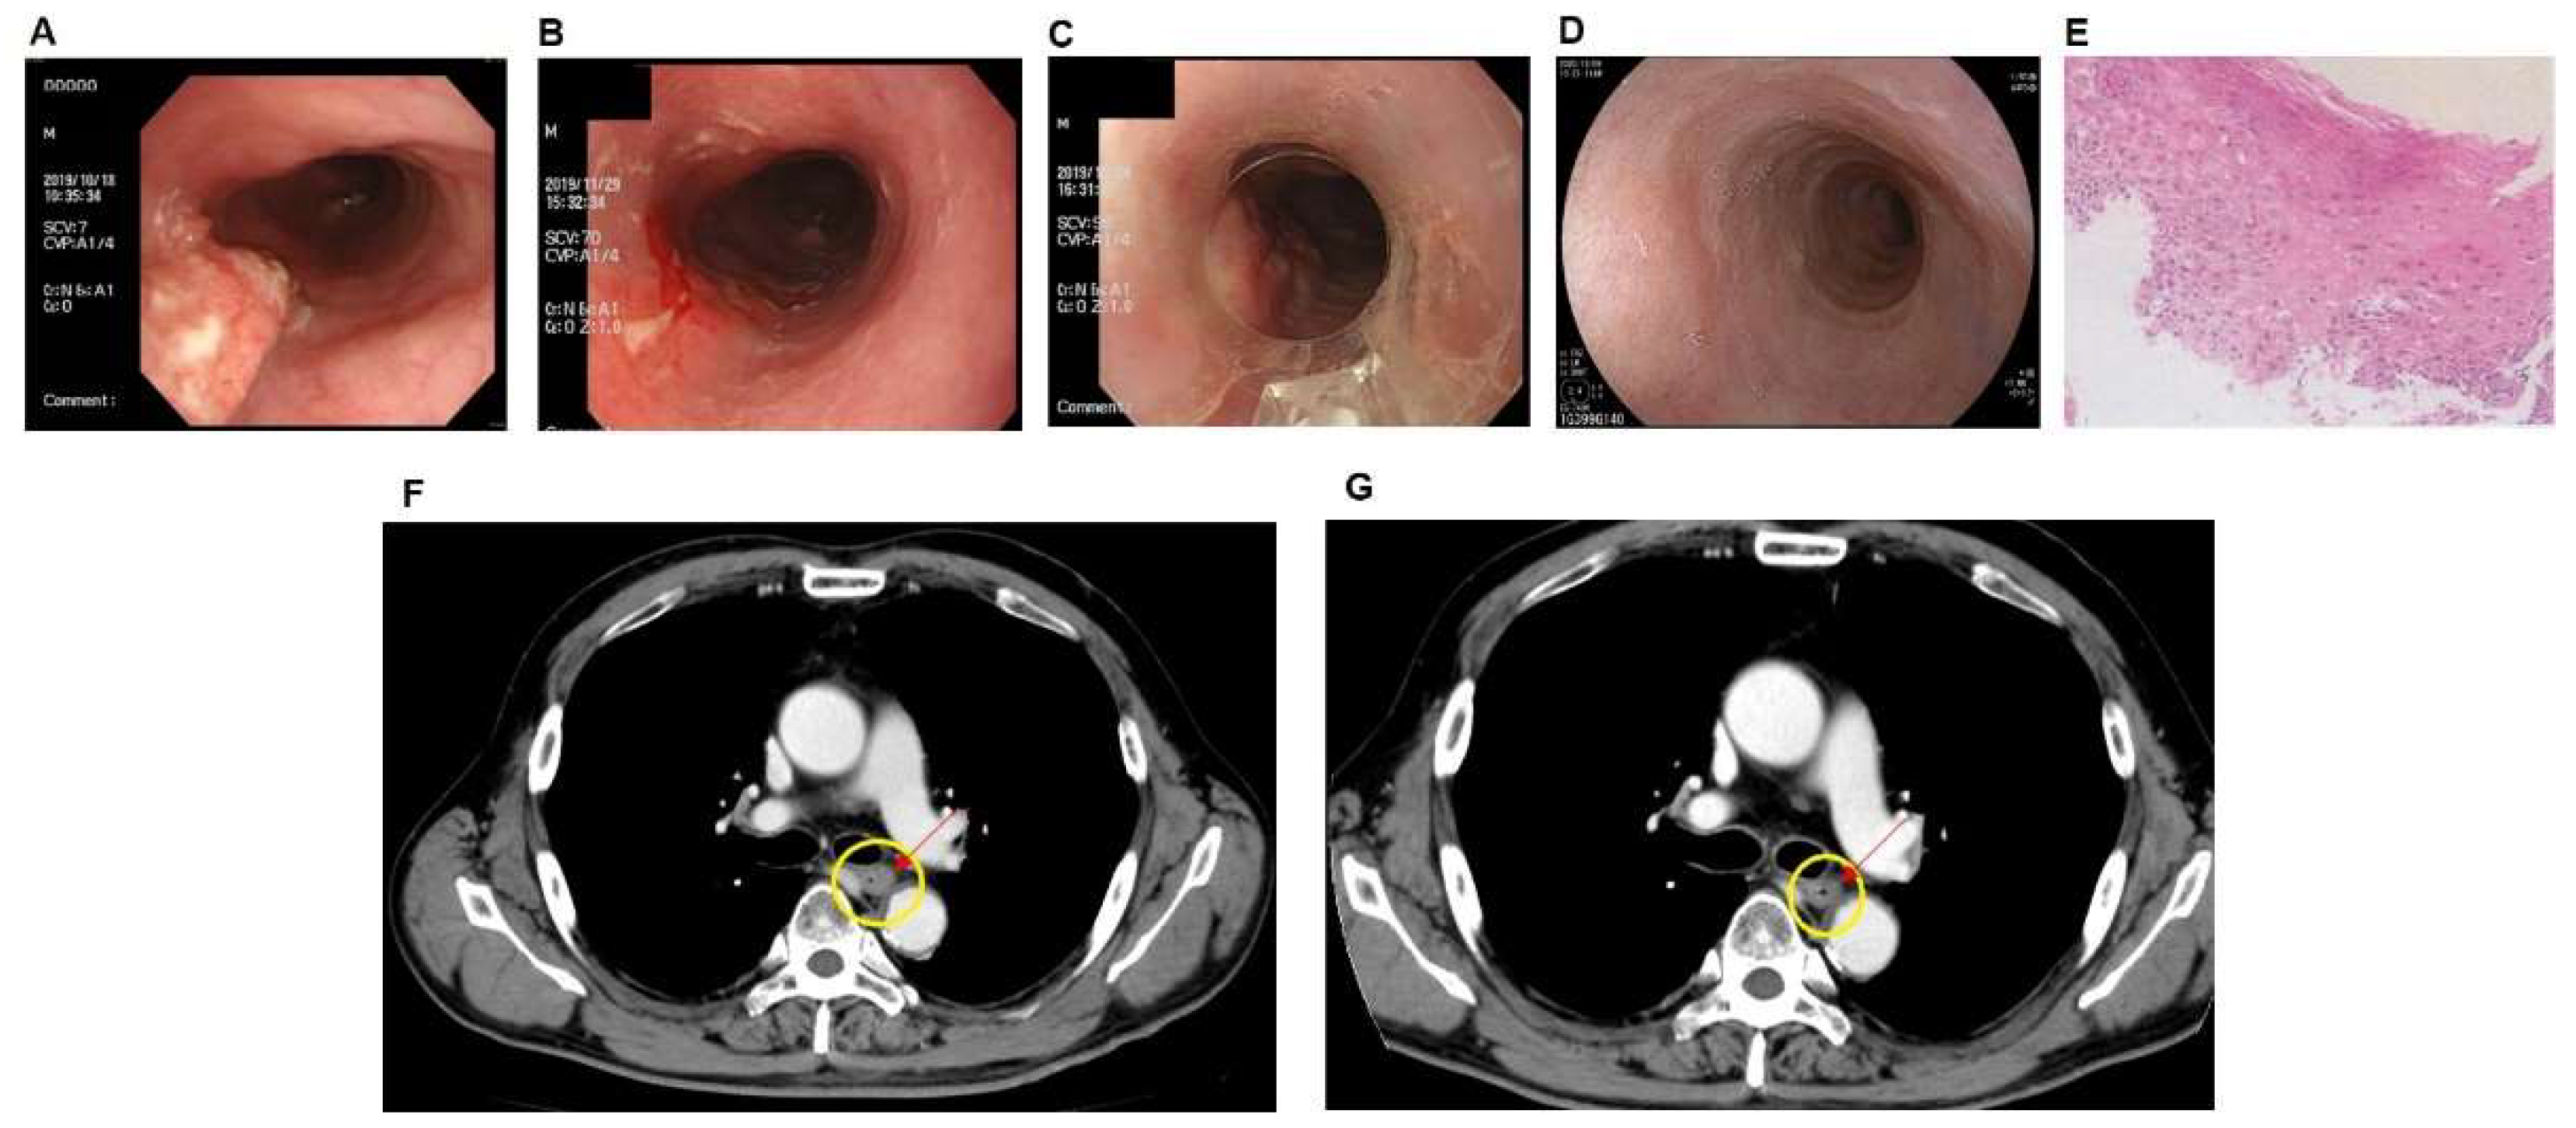

3.1. Case of PDT Combined with Radiotherapy in Middle Intrathoracic Esophagus Carcinoma